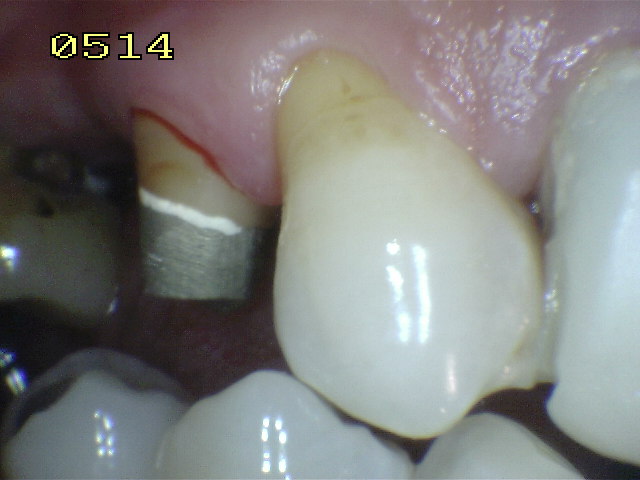

En la imagen superior se ha realizado un tratamiento de conducto y un perno muñón colado. En la siguiente se observa una corona provisoria realizada en acrílico de termocurado.